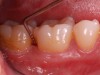

Clinical PPD is measured to the nearest millimeter by means of a graduated periodontal probe with a standardized tip diameter of approximately 0.4 mm to 0.5 mm. Several factors can influence the measurements made with periodontal probes, including: the thickness of the probe used5; the angulation and positioning of the probe depending on anatomic features, such as the contour of the tooth surface (Figure 1 through Figure 3)6; the graduation scale of the probe5; the pressure applied on the instrument during probing6; and the degree of inflammatory cell infiltration in the soft tissue and accompanying loss of collagen.7

Fig 1. Inaccurate probing angle wrongly indicates probing depth at 3 mm, which does not correspond to the radiographic finding shown in Fig 2.

Figure 1

Fig 2. Periapical radiograph showing presence of distal bone loss and calculus.

Figure 2

Fig 3. Correct angulation of the probe demonstrates 6-mm probing depth.

Figure 3